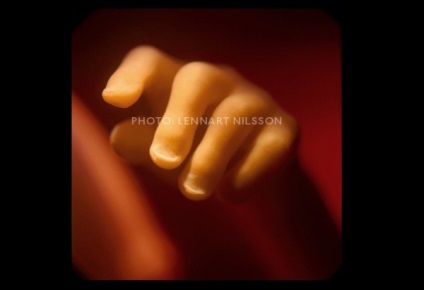

10 săptămâni. Copilul este deja cu mâinile sale pentru a explora zona

Prin pielea subțire este rețea de vase de sânge vizibile